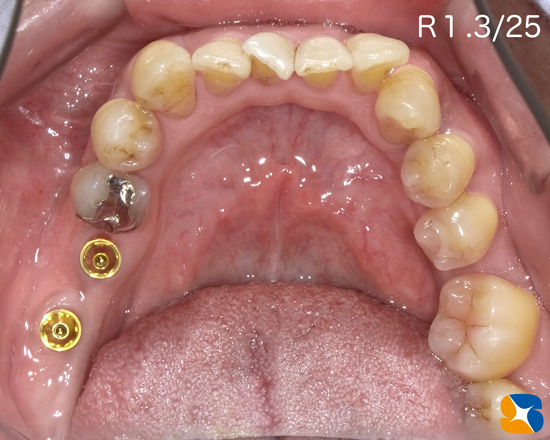

After

難症例でしたが、経過良好です。「固い物は何でもよく噛めるし、ゴルフでは飛距離が延びるようになった。人に自慢ばかりしている。今度は、うちの嫁も宜しくお願いします。」とのことで奥様も治療させて頂くことになっています。

※近々インプラントの施術予定

1/13のブログ「New Year 激しくImplant Go! スタート」の結果